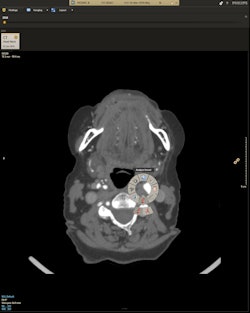

Meanwhile, Illumeo marks Philips' entry into what it calls adaptive intelligence, or the combination of artificial intelligence with domain-specific knowledge such as that found in radiology. The software records the preferences of radiologists and adapts its user interface to assist physicians by offering tools and measurements designed to meet the clinical context of the images being interpreted.

Illumeo integrates with Philips' IntelliSpace PACS reading environment, using a data analytics engine to give radiologists the most relevant case-related information from multiple sources, integrated into a single view. For example, this could include the patient problem list, lab results, prior radiology reports, imaging orders, and scanned documents from sources such as handwritten letters, as well as data from EMRs and RIS.

The software also understands the anatomical context of what the radiologist is looking at on the screen and adjusts its interface accordingly, such as by offering measurement tools if vessels are being analyzed. The software also includes a semantic labeling engine that reads and analyzes image tags and descriptions from multiple vendors, providing automatic semantic labeling and meaningful descriptions.

Radiologists can also generate dynamic reports that include 3D images or quantification of image data. Reports can be integrated with PACS and EMRs and shared as a multidisciplinary patient dashboard across a hospital enterprise to make collaboration easier for a patient's care team.